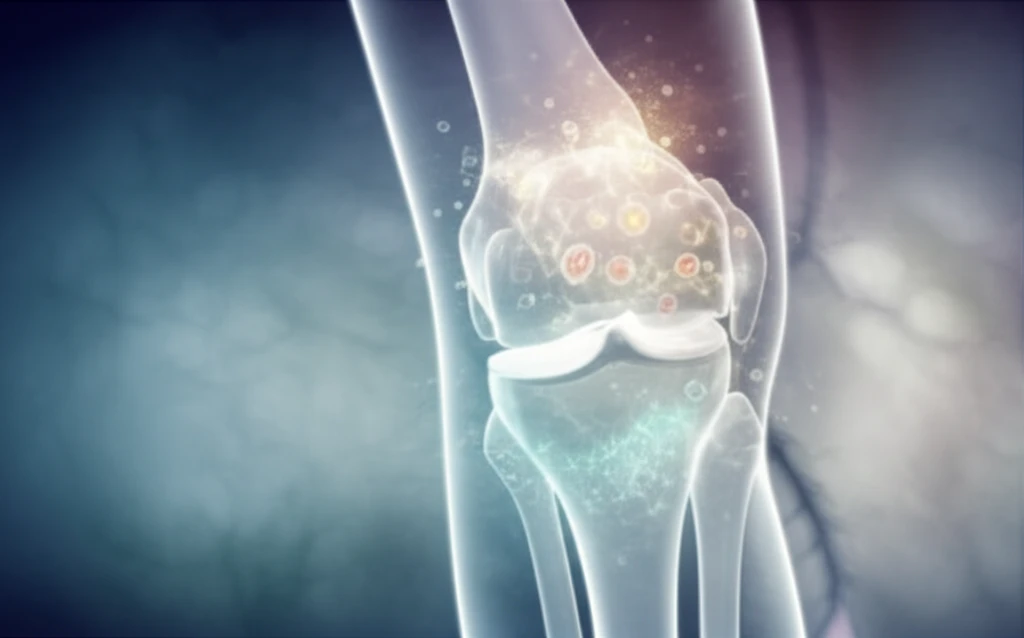

Knee pain can really put a damper on your day-to-day life, especially when it stems from cartilage issues. Focal articular cartilage defects, those small but mighty problem spots in your knee, are super common. Left unchecked, they can lead to more than just discomfort; we're talking dysfunction, joint deterioration, and even osteoarthritis. Traditional treatments have their limits, which is why there's so much buzz around biologic augmentation—using your body's own healing powers to fix things up.

Orthobiologics are emerging as a promising approach to treating these defects. These treatments aim to enhance the body's natural healing processes to repair damaged cartilage. Whether used as a standalone treatment or to boost the effects of surgery, orthobiologics offer a range of options for those seeking relief from knee cartilage issues.

Focal articular cartilage defects are localized areas of damage to the cartilage in the knee. These defects can result from injury, overuse, or general wear and tear. The cartilage, a smooth, protective tissue that covers the ends of bones in a joint, allows for nearly frictionless movement. When this cartilage is damaged, it can lead to pain, swelling, and reduced joint function.